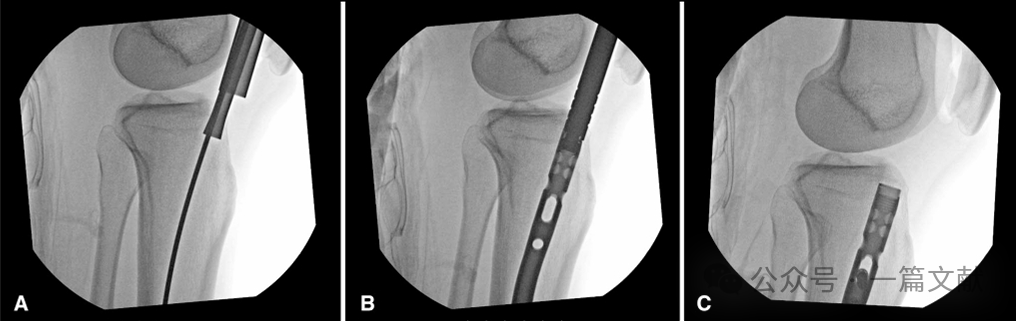

图3,术中透视标准正位片,有利于准确评价进针点,此时胫骨外侧缘平分腓骨头,如下图:

图4,“手指”技术调整导针方向:使用“手指”或空心髓内钉复位杆可以帮助骨折复位或调整导针的轨迹。在本例中,在入口扩髓后使用“手指”装置,以防止球头导丝抵住后侧皮质。其有助于提高髓内钉置入的精确性。